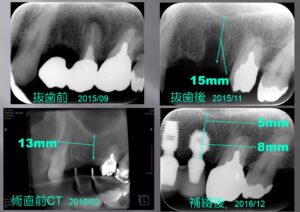

• 上顎洞底挙上術2

上顎洞底挙上術2

実際に上の顎にインプラントをしていった例をご紹介しましょう まずは上顎洞底挙上術が必要ない場合から説明しましょう。 まず左上の写真から説明しましょう。上の歯に3本つながったブリッジが入っていますが、一番左側の歯が割れてしまいまして 痛みが止 […] 本文を読む